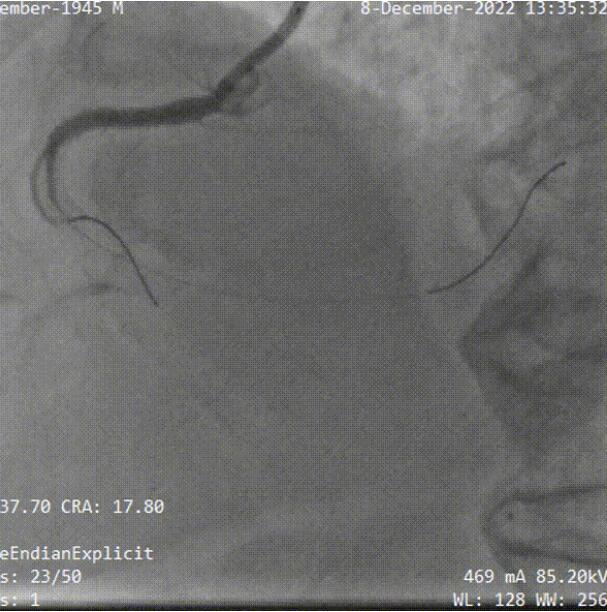

双侧造影结果:

依据3D打印指导+双侧造影,双腔微导管+UB3导丝一刻钟的时间左右成功通过CTO段到远端真腔:

术后最终结果: